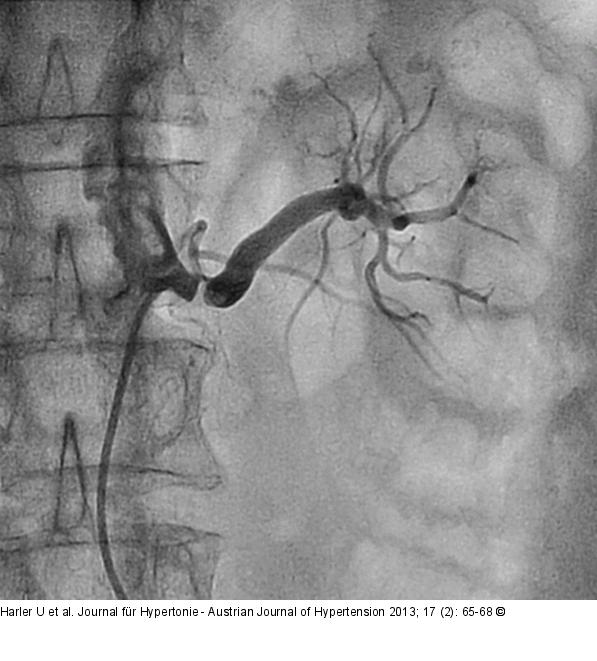

Abbildung 1: Nierenarterienstenose Präinterventionelle hochgradige Stenose (> 90 %) der linken Nierenarterie. |

Präinterventionelle hochgradige Stenose (> 90 %) der linken Nierenarterie. |